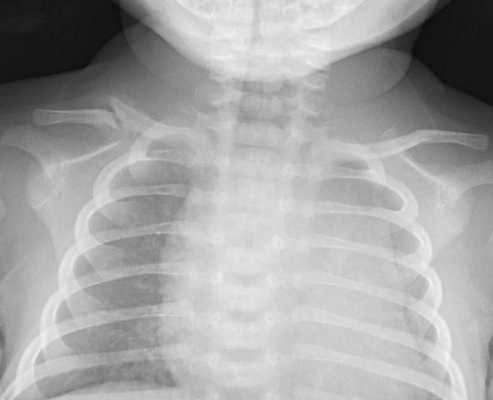

При парезе диафрагмы у новорожденного развивается одышка, парадоксальное дыхание, цианоз, выбухание грудной клети на пораженной стороне. Выявлению пареза способствует рентгеноскопия и рентгенография грудной клетки, при которых определяется высокое стояние и малоподвижность купола диафрагмы. На этом фоне у детей может развиться застойная пневмония. Лечение родовой травмы заключается в чрескожной стимуляции диафрагмального нерва; при необходимости - ИВЛ до восстановления адекватного самостоятельного дыхания.